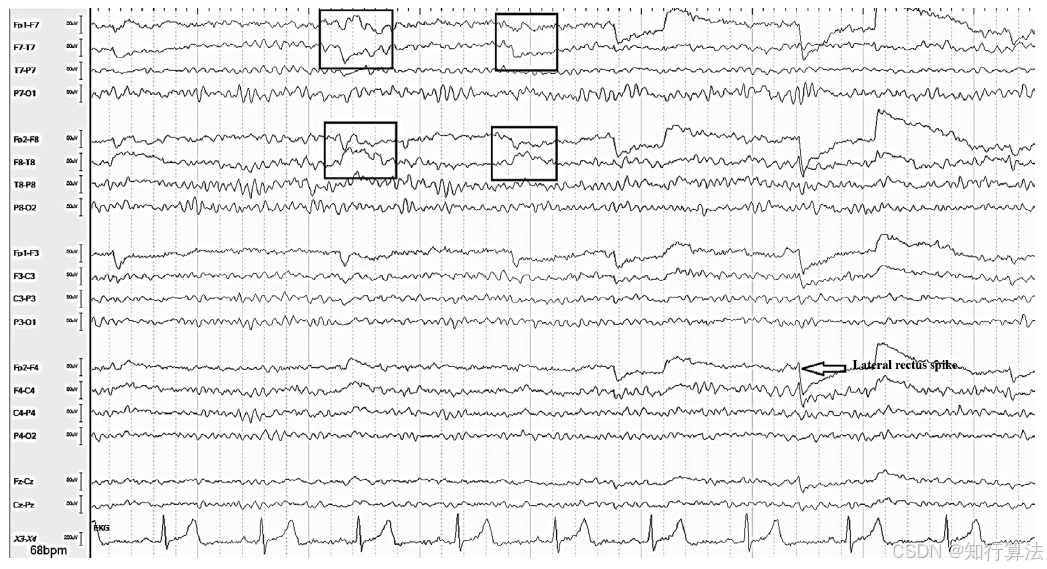

波形特征:清醒期可见规则的水平眼动(图9);REM睡眠期可见快速眼动(图11);困倦期出现慢速“划船样”眼动(图12)。

水平眼震可被误认为发作期活动(图10:左眼水平眼震在F7导联的伪迹)。

外直肌棘波(F7/F8的小尖波)常预示水平眼动。

处理方法:注意与癫痫性眼动鉴别,结合临床状态判断。

图9:水平眼球运动和外直肌电位波(F7/8)

图10:左眼外侧眼震(F7)伪影